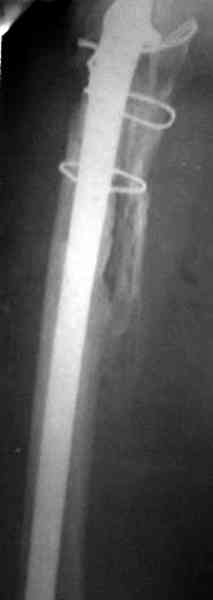

Представляю вашему вниманию снимки (прошу прошения за качество снимков) больной 48 лет с ревматоидным артритом, которой был сделан тотальный эндопротез справа,

контрольный снимок сделали только на 21день после операции (№1) и с интервалом 5 дней второй снимок (№2)

Судя по всему, произошел раскол наружной стенки бедра и ножка находится вне костного канала. В таком случае

решение одно - удаление ножки и установка новой в расчете на дистальную фиксацию. Конктреную модель подсказать тяжело из-за низкого качества Р-грамм.

№3-6 снимки с осложнением